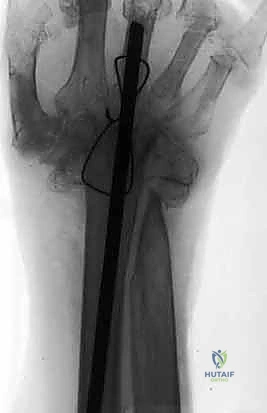

خطوات العملية الجراحية بالتفصيل: كيف يتم التثبيت؟

تُجرى عملية تثبيت مفصل الرسغ الكلي تحت التخدير العام أو التخدير الموضعي للذراع (Block)، وتستغرق عادة من ساعتين إلى ثلاث ساعات. يتبع الأستاذ الدكتور محمد هطيف الخطوات الدقيقة التالية:

4. وضع الرسغ في الزاوية الوظيفية المثالية

لا يتم تثبيت الرسغ بشكل مستقيم تماماً. بدلاً من ذلك، يقوم الدكتور هطيف بتثبيته في وضعية "البسط الخفيف" (Slight Extension)، عادة بزاوية تتراوح بين 10 إلى 15 درجة للخلف. هذه الزاوية هي الوضع الطبيعي لليد عند الإمساك بالأشياء بقوة، وتضمن للمريض أقصى قدرة على استخدام يده في حياته اليومية (مثل الإمساك بكوب، أو استخدام الأدوات).

5. التثبيت بالشريحة والمسامير (Plate Fixation)

يتم استخدام شريحة معدنية خاصة (Wrist Fusion Plate)، غالباً مصنوعة من التيتانيوم، مصممة خصيصاً لتناسب تشريح الرسغ. يتم تثبيت هذه الشريحة بمسامير قوية تمتد من عظم الكعبرة في الساعد، مروراً بعظام الرسغ، وصولاً إلى العظم المشطي الثالث (Third Metacarpal) في اليد. هذا التثبيت الصلب يمنع أي حركة ويسمح للعظام بالالتحام لتكوين كتلة واحدة صلبة.

6. الإغلاق (Closure)

بعد التأكد من قوة التثبيت باستخدام جهاز الأشعة السينية داخل غرفة العمليات (C-arm)، يتم إعادة الأوتار إلى مكانها، وإغلاق الشق الجراحي بغرز تجميلية دقيقة لتقليل الندبات، ثم يتم وضع اليد في جبيرة أو دعامة صلبة لحمايتها.